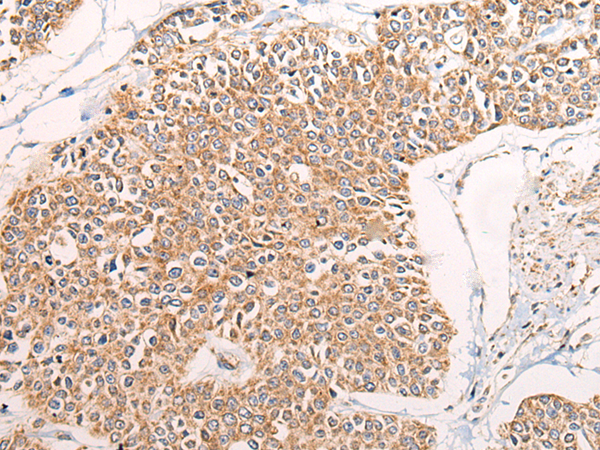

IHC positive control: |

IHC Recommend dilution: |

40-200 |